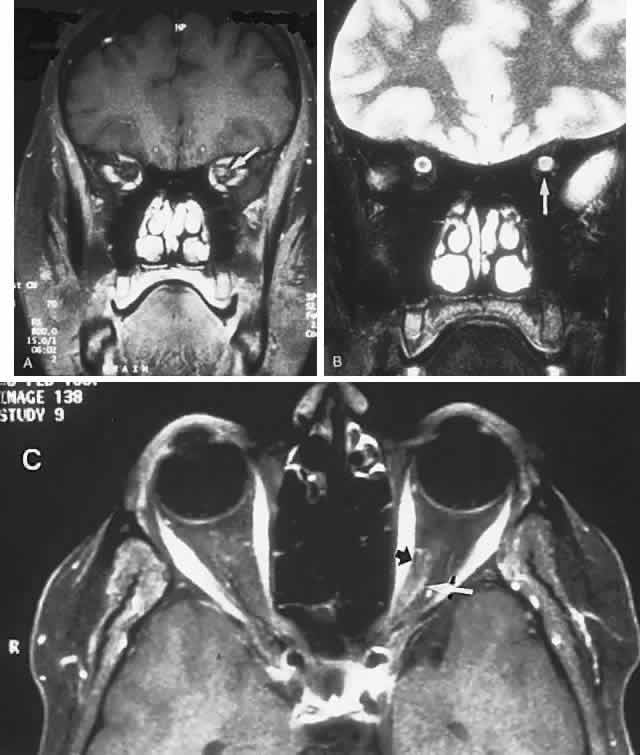

In contrast to transient symptoms and signs of retinal microembolic episodes, a condition of chronic ocular hypoxia (ocular ischemic syndrome) occurs less frequently, resulting from diffuse vascular occlusive disease of the aortic arch or common carotid artery. Acute or chronic occlusion with insufficient collateralization produces an ischemic pseudo-inflammatory uveitis, which variably includes an injected painful globe, corneal edema, aqueous flare and cells, a mid-dilated fixed pupil, rubeosis and iris atrophy, rapidly advancing cataract, either hypotony or elevated intraocular pressure (“neovascular glaucoma”), retinal microaneurysms and new vessel formation, posterior pole and mid-peripheral blot hemorrhages, macular edema, venous dilation and “sausaging,” cytoid infarcts (cotton-wool spots) of the nerve fiber layer, and arterial occlusions (Fig. 7; see Table 4). The hypoxemic fundus changes constitute a picture of venous stasis (low-pressure) retinopathy, perhaps the commonest ocular sign of chronic carotid obstruction.

Fig. 7. Ocular hypoxia with subacute carotid occlusion. The patient complained of a painful red eye. A. Anterior segment shows an irregular, fixed pupil and iris rubeosis (arrows). B. Fundus demonstrates combined retinochoroidal infarction with acute excavation of the optic disc. Arteriography revealed right internal carotid occlusion.